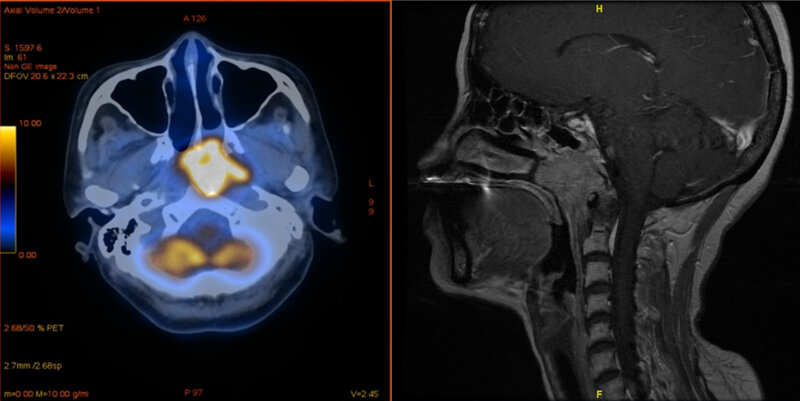

Viele Krebszellen sind dazu in der Lage, die Immunantwort des Körpers zu unterlaufen. Sie betätigen dazu eine Art Knopf auf den Immunzellen, den PD-1-Rezeptor. Dadurch schalten sie diese körpereigenen Abwehrtruppen gewissermaßen ab. Mit Medikamenten lassen sich die PD-1-Rezeptoren blockieren. Das Immunsystem kann so den Tumor besser bekämpfen. Bei der Impfung gegen Covid wird ebenfalls die Immunantwort stimuliert, wobei der PD-1-Rezeptor involviert ist. „Man befürchtete, dass die Impfung sich nicht mit einer Anti-PD-1-Therapie vertragen könnte“, erklärt Dr. Jian Li vom Institut für Molekulare Medizin und Experimentelle Immunologie (IMMEI) am Universitätsklinikum Bonn. „Diese Gefahr besteht insbesondere bei Nasenrachenkrebs, der genau wie das SARS-Cov-2-Virus die oberen Atemwege befällt.“

Nasenrachenkrebs ist hierzulande recht selten. In Südchina und anderen Ländern Südostasiens ist die Erkrankung dagegen weit verbreitet. Als Gründe vermutet man unter anderem den häufigen Einsatz von Klimaanlagen in den feuchten und heißen Regionen. Auch Ernährungsfaktoren scheinen eine wichtige Rolle zu spielen. In Taiwan gilt Nasenrachenkrebs inzwischen bei jungen Männern als eine der häufigsten Todesursachen.